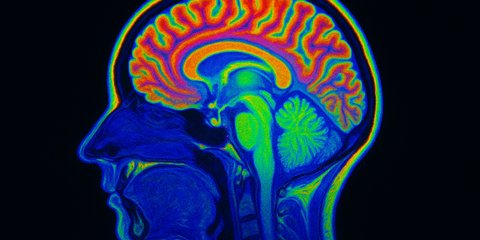

Sains punya bukti tentang hasil MRI dari otak orang-orang psikopat.

Sebuah penelitian gabungan yang dilakukan Universitas New Mexico dan MIND Research Network mengungkap hasilnya.

Mereka melakukan penelitian itu di sebuah penjara. Di sana, mereka menggunakan MRI untuk memindai otak para tahanan.

Penelitian tersebut membandingkan otak 20 narapidana yang terdiagnosis psikopati dengan otak 20 narapidana lain yang melakukan kejahatan serupa namun tidak terdiagnosis psikopati.

“Kombinasi kelainan struktural dan fungsional memberikan bukti kuat bahwa disfungsi otak yang diamati dalam sirkuit sosial-emosional penting ini merupakan karakteristik stabil dari pelaku psikopat,”

UW-Madison psychology Professor Joseph Newman.

Hal serupa juga diamini oleh penelitian dari School of Medicine And Public Health. Hasil risetnya itu melaporkan bahwa terdapat perbedaan struktur dan fungsi pada otak seorang psikopat.Dalam studinya seorang psikopat memiliki masalah pada Ventromedial Prefrontal Cortex (vmPFC), merupakan bagian otak yang bertanggung atas sentimen, empati, rasa bersalah, dan amigdala yang mengatur rasa takut serta kecemasan.

Selain itu, dalam penelitian Journal of Neuroscience, Newman dan Koenigs menunjukkan seorang psikopat selain memiliki masalah dalam vmPFC, ternyata jaring vmPFC juga memiliki kerusakan yang membuat seorang psikopat dalam menyelesaikan masalah menggunakan cara yang kriminal.

Secara keseluruhan memang seorang yang psikopat disebabkan oleh kelainan pada sistem otak. Bahkan menurut ilmu mengenai saraf manusia, hal tersebut kembali mengarah karena adanya perbedaan cara kerja dari otak.